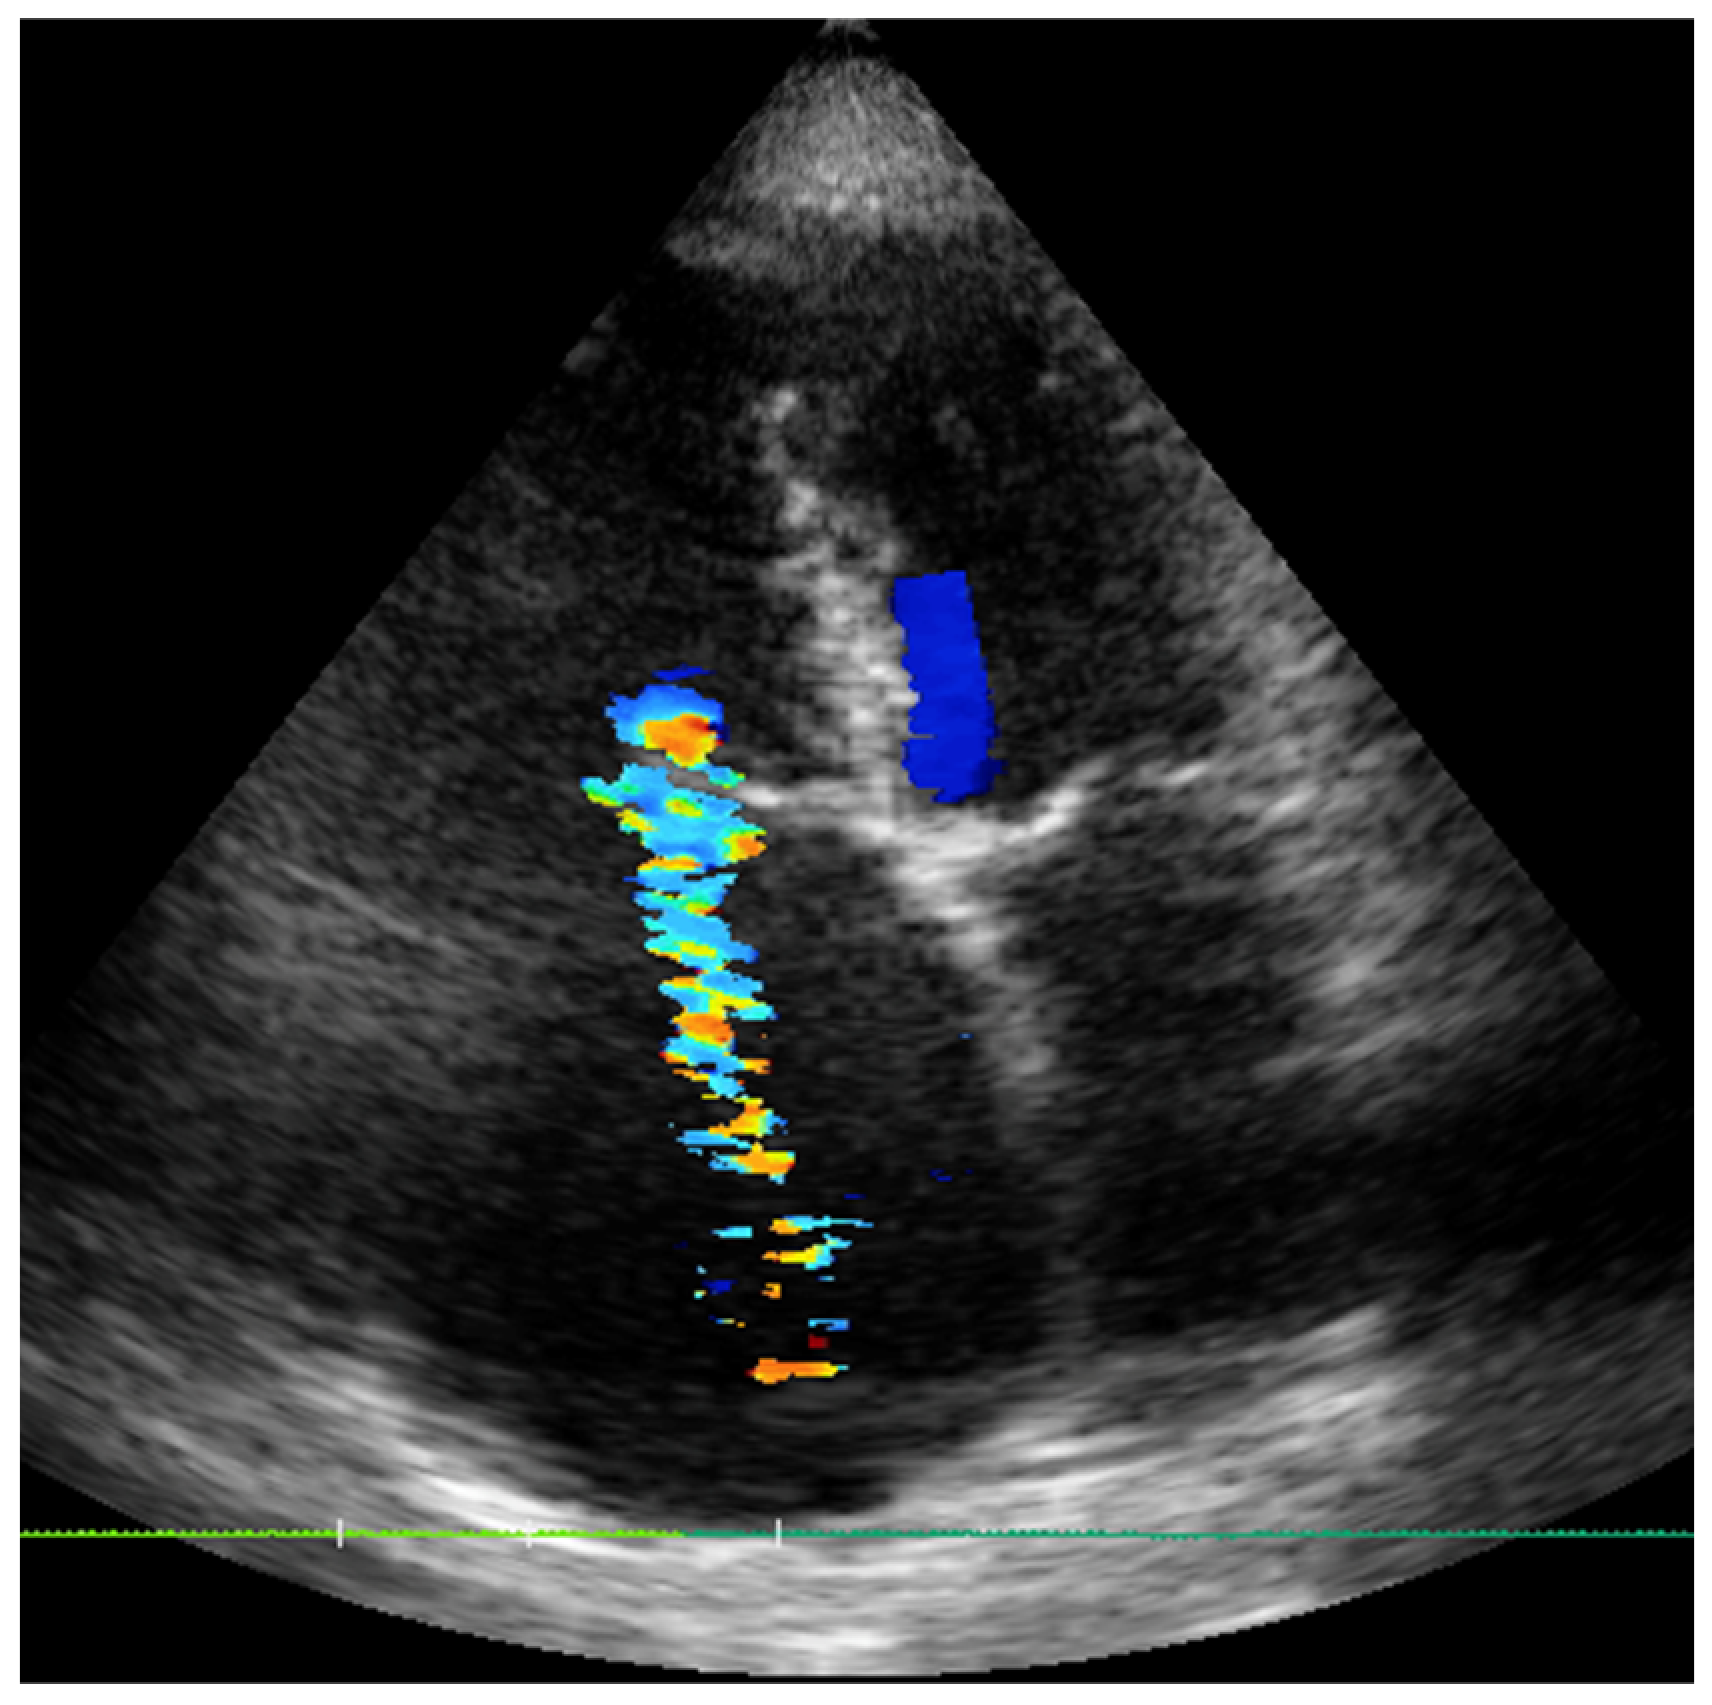

2.1. Case 1